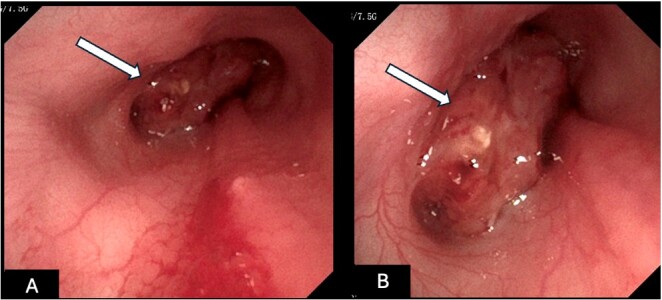

Epistaxis is defined as bleeding from the nasal cavity and can be related to systemic causes leading to coagulation disorders, most commonly hemoparasitosis, or to localized changes in the nasal cavity itself (e.g., intranasal neoplasms). Transmissible venereal tumors (TVT) are malignant round cell neoplasms characterized by an anomalous proliferation of tumor cells disseminated mainly by direct contact between animals. Although transmitted sexually, transmission through contact with mucous membranes and skin tissue can also occur, including the nasal cavity. Although rare, it can have significant clinical implications because it is difficult to diagnose. The diagnosis is made by physical examination, imaging tests (computed tomography and rhinoscopy), and histopathological analysis, which is the gold standard. Treatment is based on the use of chemotherapeutic agents, with vincristine as the drug of choice. This study reported a case of intranasal TVT in a 4-year-old French bulldog and addressed its clinical characteristics, diagnosis, and treatment. It also reported the importance of early recognition of the condition and changes in imaging tests to better understand and manage this atypical presentation.

Abstract Image